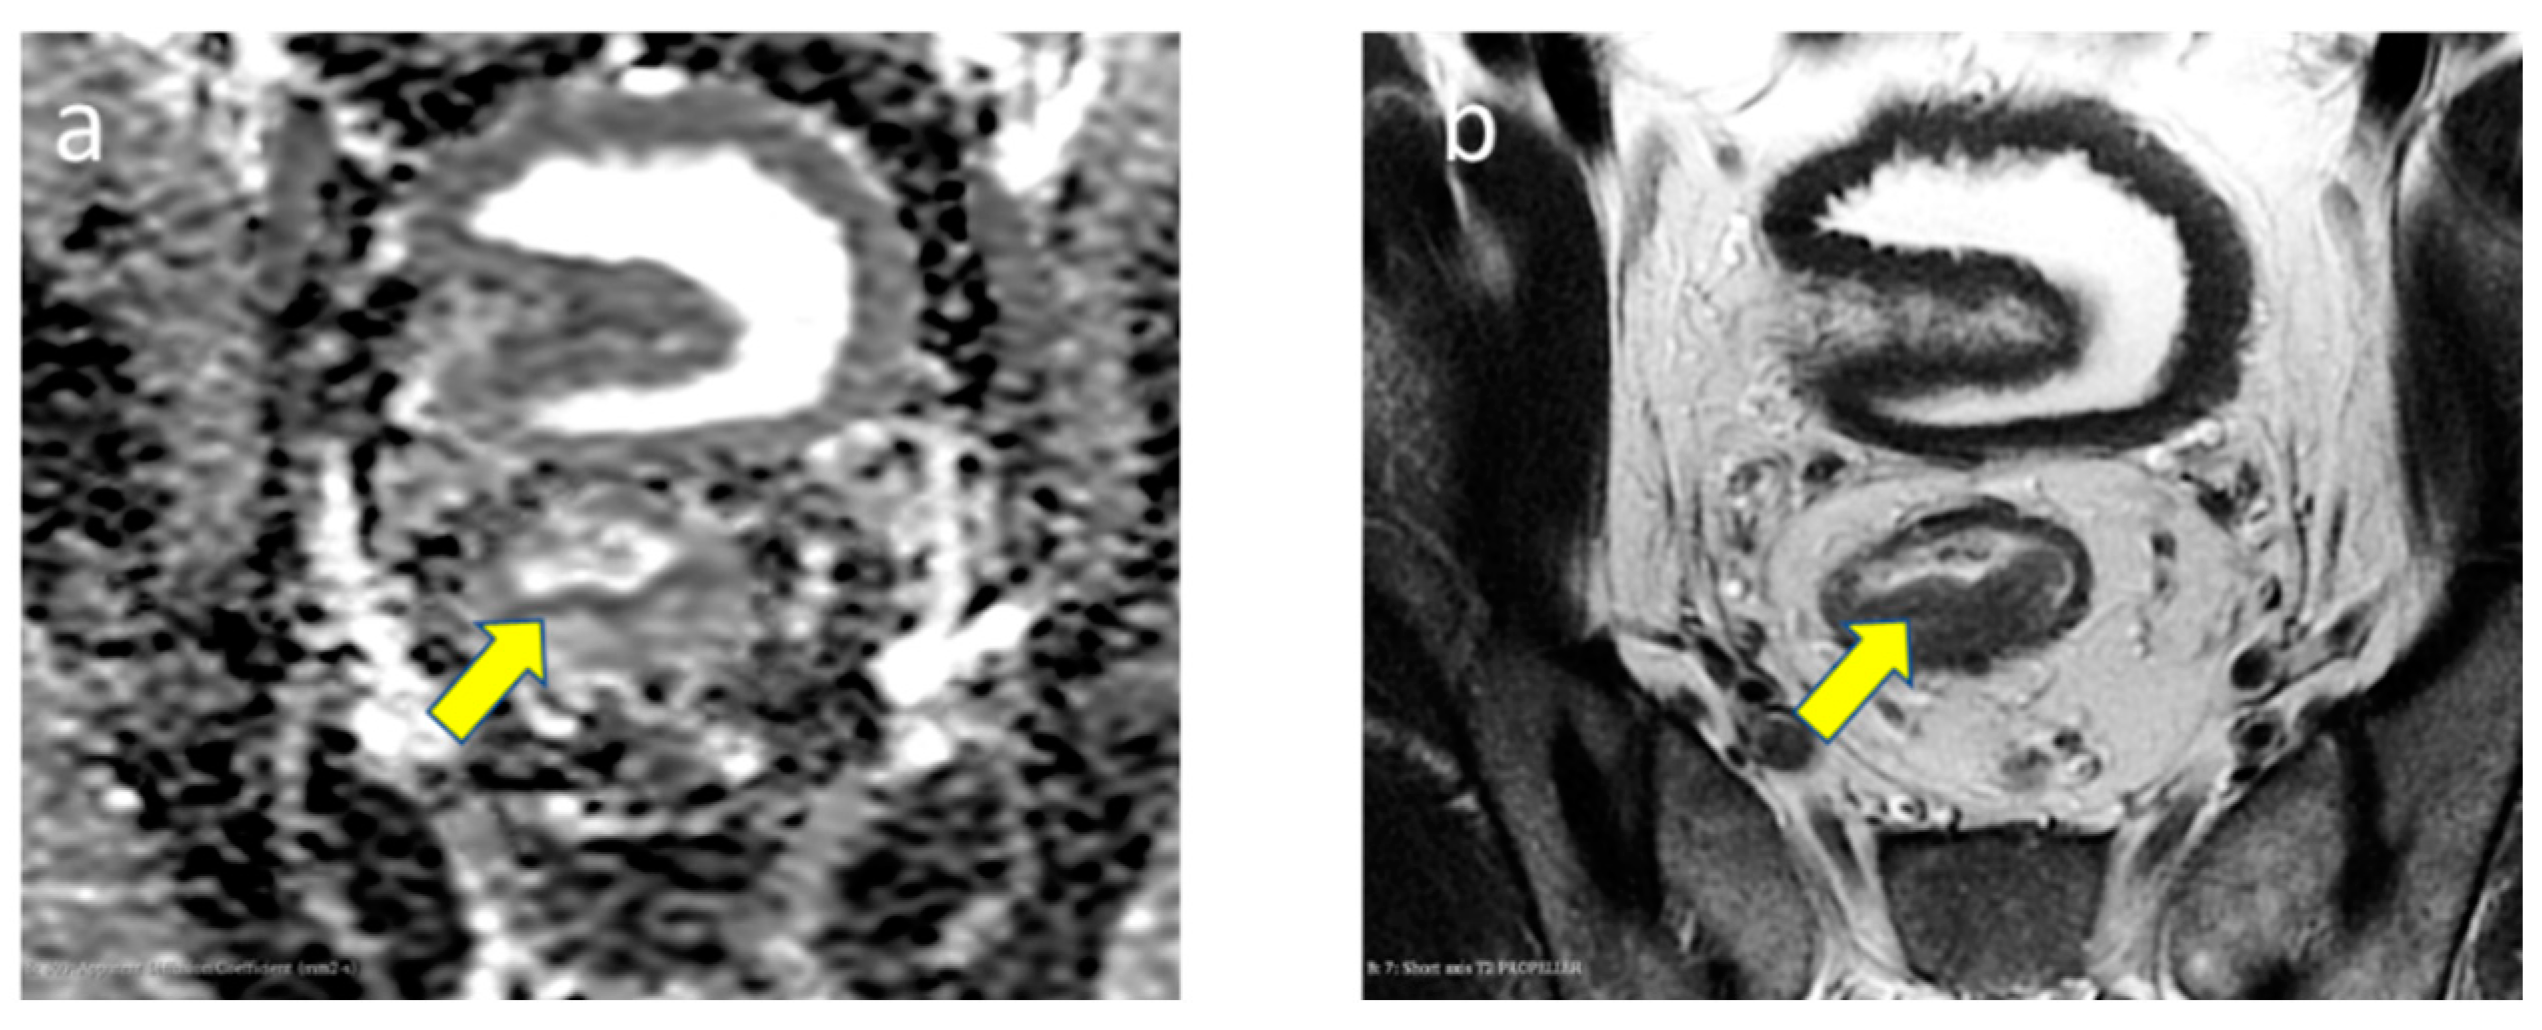

3.2.5. EMVI Status